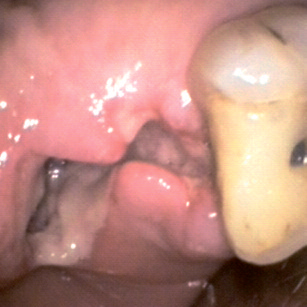

Septodont Alveogyl (Септодонт Альвожил) — сильное антисептическое средство на основе йодоформа в соединении с местным анестезирующим средством длительного действия (бутоформом), предназначенное для остановки кровотечения, ускорения заживления и облегчения боли пациента после сложного или травматичного удаления зуба, а также при сухости зубной лунки.

Альвеолярные компрессы Альвожил изготовлены с применением папоротника Пенгхавар-Джамби, волокнистые ткани которого легко заполняют весь объем альвеолы и обеспечивает хорошее прилегание к стенкам лунки. Средство Септодонт Альвожил применяется в один этап и не требует как наложения швов, так и особого ухода, кроме наблюдения за процессом заживления.

Препарат не оставляет язв на слизистой оболочке. Septodont Alveogyl оказывает действие в течении нескольких часов, после чего остатки средства полностью рассасываются.

Показания к применению

Septodont Alveogyl может использоваться в качестве послеоперационной дезинфицирующей повязки после сложного или травматичного удаления зуба у пациентов с альвеолитом.

Инструкция по применению

Возьмите гранулу (около 0,20 г) пасты Альвожил, скатайте в шарик и аккуратно поместите ее в подготовленную лунку. Не накладывайте швы.